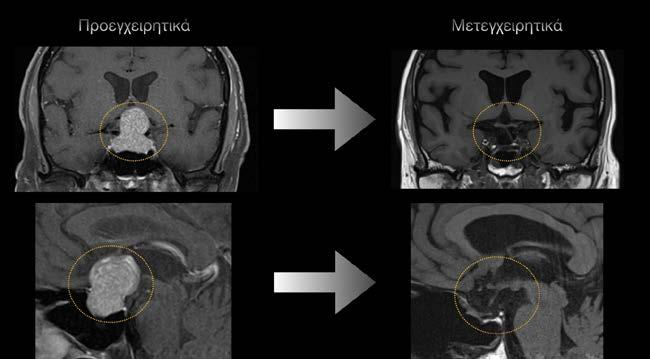

Τα αποτελέσματα της σύγχρο

νης ενδοσκοπικής χειρουργικής

είναι ιδιαίτερα ενθαρρυντικά.

Σε ποσοστό που ξεπερνά το

80% των μικρών όγκων (μικροαδενωμάτων) επιτυγχάνεται ύφεση της νόσου (βιοχημική ύφεση/remission).

Ή ανάρρωση είναι ταχεία, με νοσηλεία συνήθως 2-3 ημερών, και η επέμβαση δεν αφήνει κανένα εξωτερικό σημάδι, επιτρέπο ντας τη γρήγορη επιστροφή στις καθημερινές δραστηριότητες.